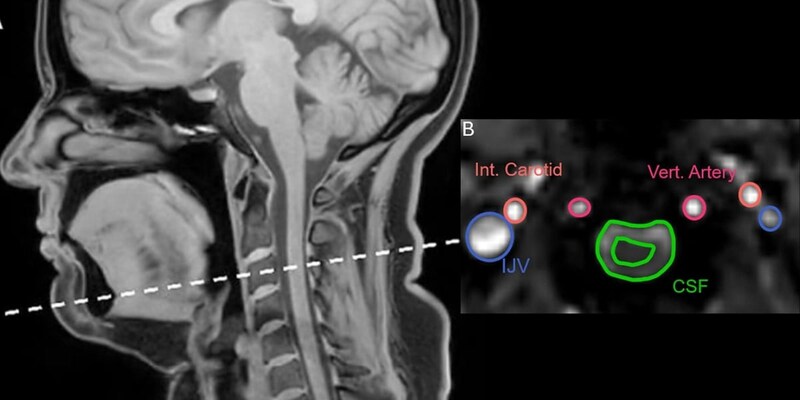

そのあいだに首の上の方、首の骨でいうと三番目あたりで、脳脊髄液の流れと内頸静脈を流れる血液の流れが、どの向きにどれくらいの速さで動くのかを、別々に連続的に記録しました。

ところが、流れの「向き」までくわしく調べると、深呼吸とあくびでは、はっきりした違いが見つかりました。

まず深呼吸で大きく息を吸ったときには、脳脊髄液は頭の方へ向かって流れ、血液は首から胸の方へ向かって流れ出していくパターンが多く見られました。

簡単にいうと、深呼吸では「水は上へ、血は下へ」という結果です。

これに対して、多くのあくびでは、口を大きく開けてぐっと息を吸い込む瞬間に、脳脊髄液と静脈の血液がどちらも頭から首へ、つまり下のほうへ流れるというパターンがみられました。

頭の中の水路からも、血の通り道からも、中身がまとめて首の方に引っぱり出されるような動きです。

深呼吸が「水は上へ、血は下へ」ならば、あくびは「水は下へ、血も下へ」という傾向が見えてきたのです。